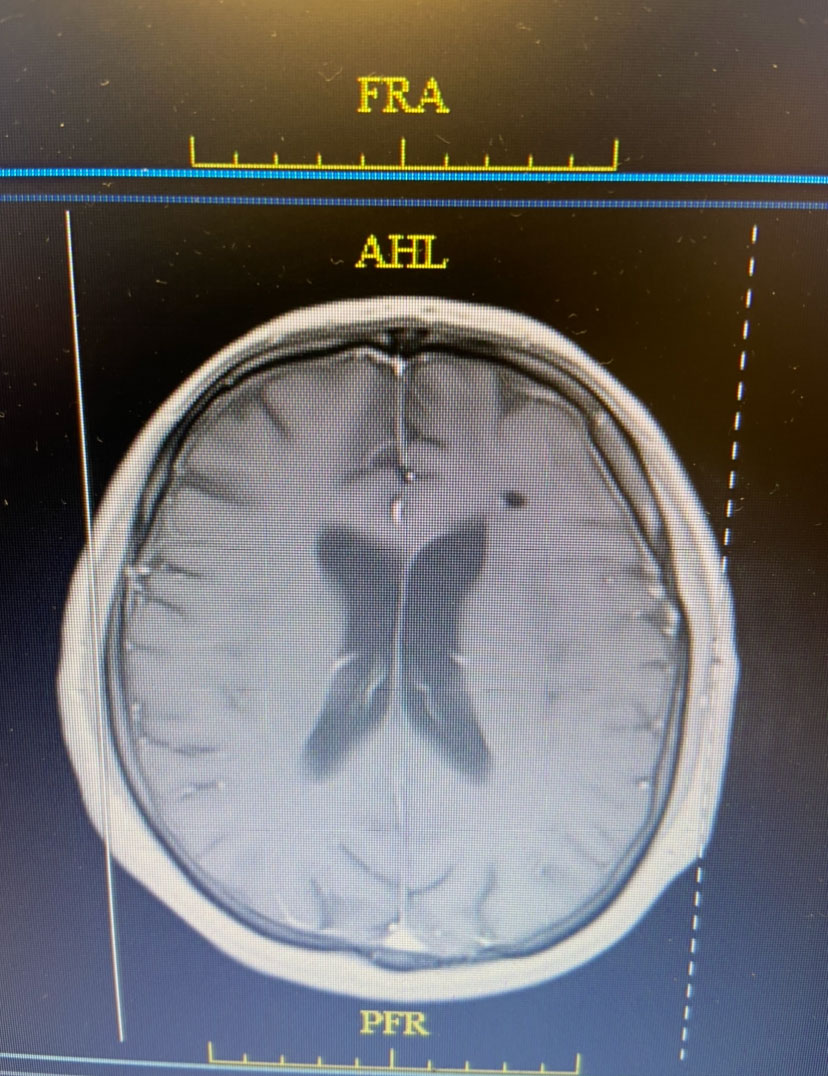

Postoperatively, the patient was started on broad spectrum IV antibiotics, under the supervision of an Infectious Disease consult. Clinically, the patient gradually recovered. Within weeks, the patient had fully recovered and was neurologically intact. Gram stains were suspicious for the presence of bacteria (encapsulated cocci). Cultures never grew out any organisms. The patient was treated with several weeks of broad spectrum IV antibiotics. The patient made a full recovery. (Image 3, axial post contrast MRI from 3 months post-op shows resolution of brain abscess and surrounding edema. )

Image 3: Axial post contrast MRI from 3 months post-op shows resolution of brain abscess and surrounding edema.